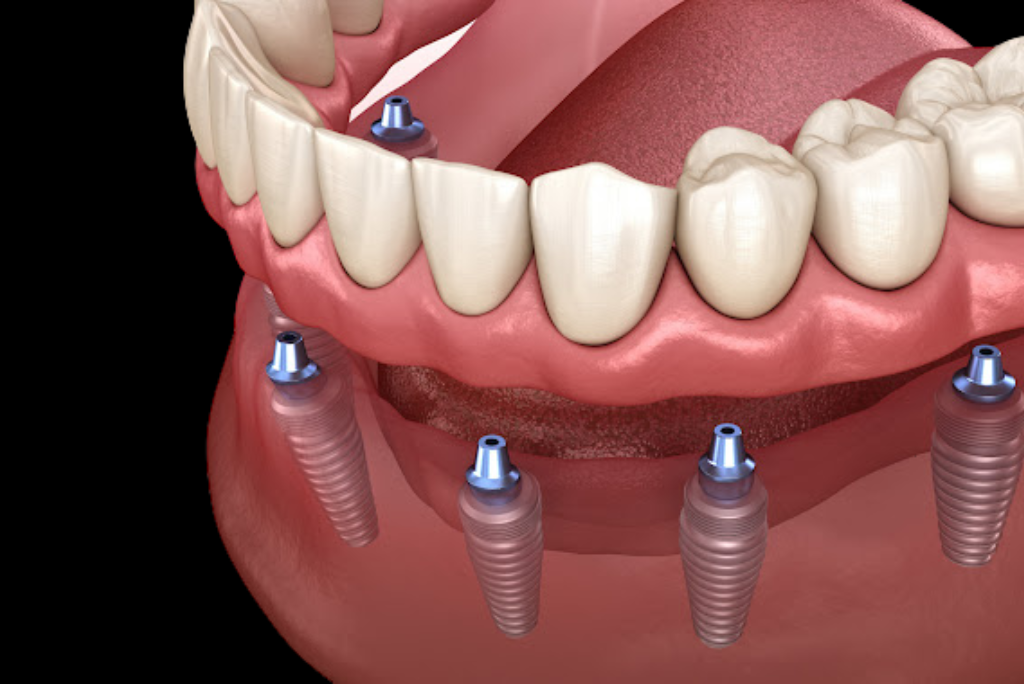

La Rehabilitación Oral es una especialidad de la odontología que se dedica a restaurar de manera integral la salud, función y estética de la boca, especialmente cuando se presentan problemas complejos que involucran múltiples dientes o toda la dentadura. Su objetivo principal es devolver al paciente una sonrisa saludable, funcional y atractiva, abordando situaciones como dientes severamente dañados, desgastados o fracturados, ausencia de varios dientes, problemas de mordida y alineación dental, trastornos temporomandibulares y desgaste dental excesivo debido al bruxismo.

En nuestra clínica, ofrecemos una amplia gama de servicios de Rehabilitación Oral para abordar problemas dentales complejos y devolver a nuestros pacientes una sonrisa radiante y funcional. Con un enfoque integral y personalizado, nos aseguramos de proporcionar soluciones efectivas y seguras para cada uno de nuestros pacientes.

- Más de 10 años de experiencia en implantología de alta calidad.

- Nos eligen por nuestra precisión, atención personalizada y calidad en el material de nuestros implantes.